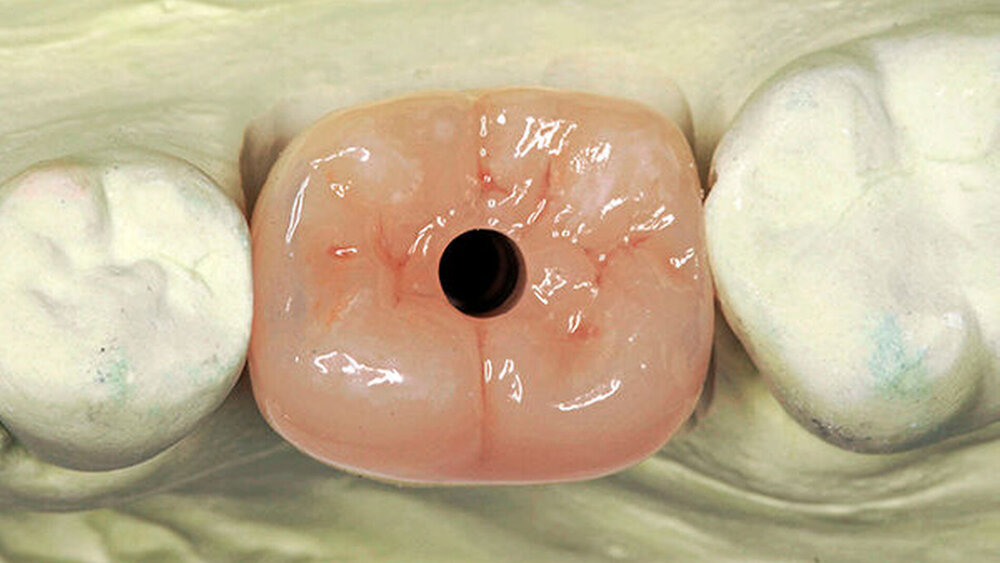

Ja, denn beide haben ihre Pluspunkte. Für unsere Chairsideversorgungen unmittelbar nach der Freilegung wählen wir zum Beispiel ausschließlich konische Innenverbindungen, um sicherzugehen, dass kein Weichgewebe eingeklemmt wird.

Es besteht jedenfalls ein Risiko, das ich nicht eingehen möchte. Mit einem verzögerten CEREC-Protokoll wäre man auch mit Butt-Joints auf der sicheren Seite. Nach dem Einbringen des Gingivaformers sollte vor der definitiven Versorgung eine Woche verstreichen, bis das Gewebe soweit adaptiert ist.